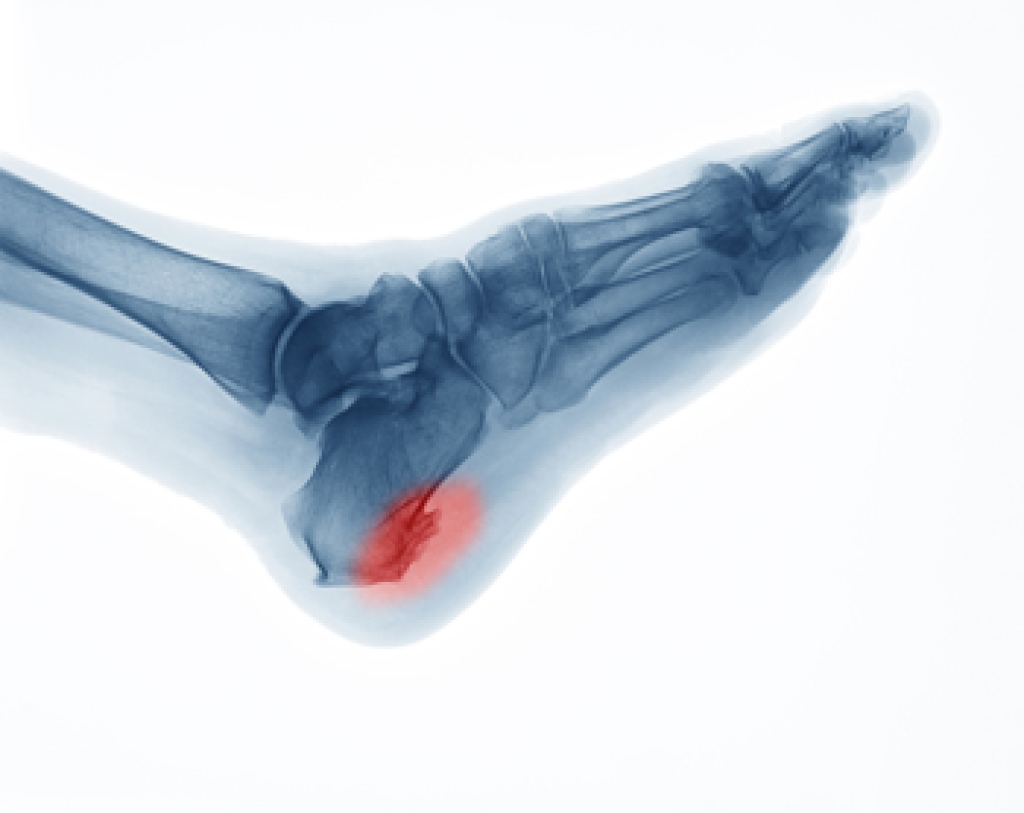

- Plantar fasciitis is also another common injury.